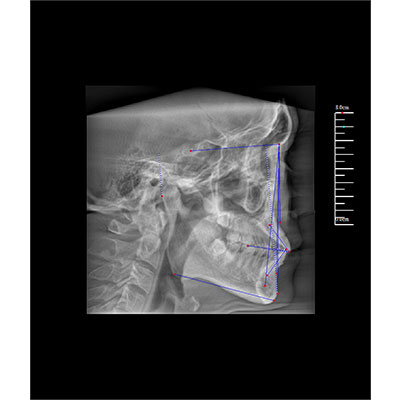

该款牙科CBCT产品采用动态平板探测器,获得三维图像的同时还具有数字化全景功能,广泛应用于口腔颌面外科、正畸科、正颌外科、种植科、牙体科、颞下颌关节科等术前术后。

三维重建任意断层

专有三维重建算法,可提供任意位置高清断层影像。

多平面组合重建

可同时观察轴向面、冠状面和矢状面图像,方便临床诊断。

Clinical picture

临床图片